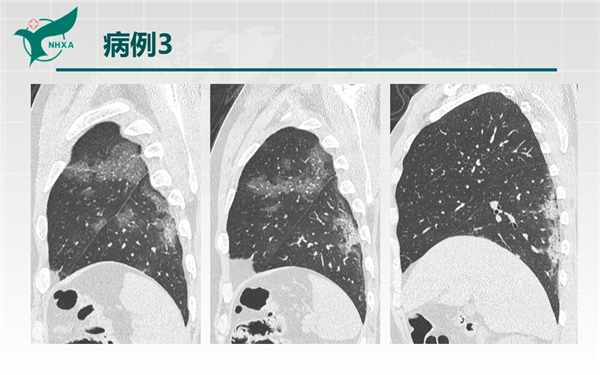

【病例分享】新型冠狀病毒肺炎3例(西安市第九醫(yī)院)

幻燈片6.jpg